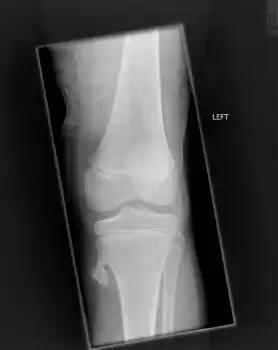

-

Osteochondroma arising from the thigh bone, near the knee -